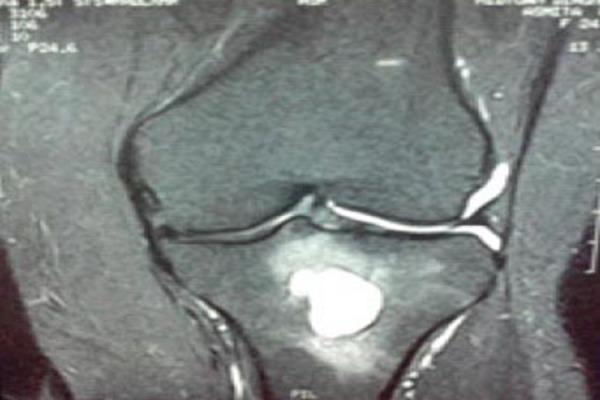

We report a rare case of malakoplakia of bone of upper end tibia in a 24 year old female with 1 month complaints of pain in the knee.

The importance of this case report lies in the fact that malakoplakia can mimic benign lytic lesion and we need not be over aggressive while treating these patients. These can be treated with course of antibiotics [2].